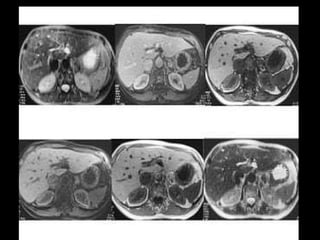

PROTOCOLO hígado graso AXIAL in phase y out phase AX T1 y AX fat sat +SAG T2  CON   GADOLINIO :  COR T1+AX T1(DIN) SAT: NO  FASE: RL THK: 4MM  COIL:  GAP: (FACTOR 1.4)  FOV: 40 CM NEX:2 SINCRONIZACION RESPIRATORIA EN 3 O 4 CICLOS ALE

PROTOCOLO hemocromatosis AXIAL supresión grasa /AX multieco en higado COR T2 AX T1 +SAG T2  CON   GADOLINIO :  COR T1+AX T1 SAT: NO  FASE: RL THK: 4MM  COIL:  GAP: (FACTOR 1.4) 1MM FOV: 40 CM NEX:2 SINCRONIZACION RESPIRATORIA EN 3 O 4 CICLOS ALE

PROTOCOLO pancreas/ riñon AXIAL fat sat /AX in phase out phase AX T1 +SAG T2  COR T2, CON   GADOLINIO :  COR T1+AX T1(DIN) SAT: NO  FASE: RL THK: 4MM  COIL:  GAP: (FACTOR 1.4) 1MM FOV: 40 CM NEX:2 SINCRONIZACION RESPIRATORIA EN 3 O 4 CICLOS ALE